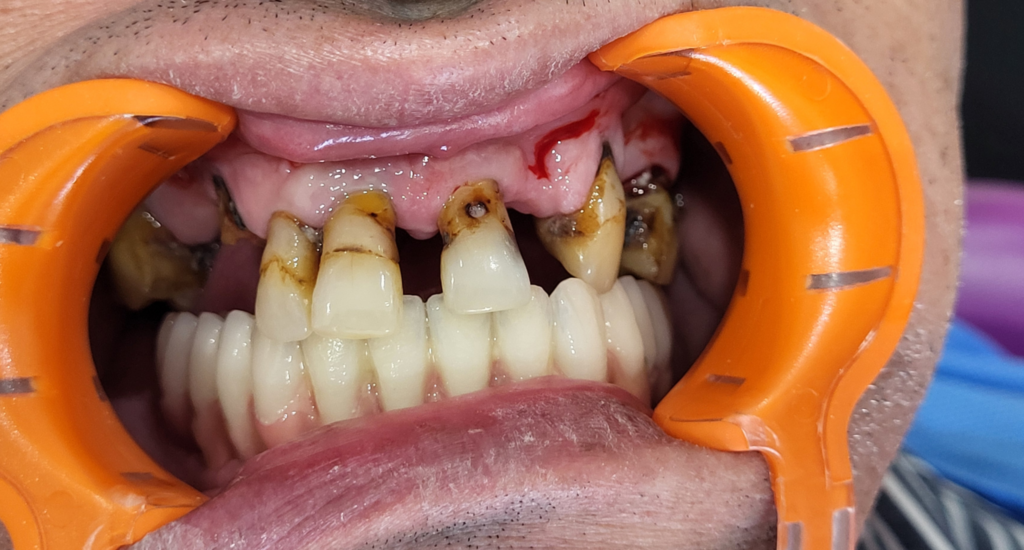

Kyste intra-osseux mandibulaire : extraction, énucléation et réhabilitation implantaire immédiate

Problème : kyste intra-osseux associé à la perte de toutes les dents de l’arcade inférieure.

Conduite à tenir (CAT) : extraction des dents restantes, énucléation du kyste, puis mise en place de 5 implants avec mise en charge immédiate, le tout réalisé en une seule séance.